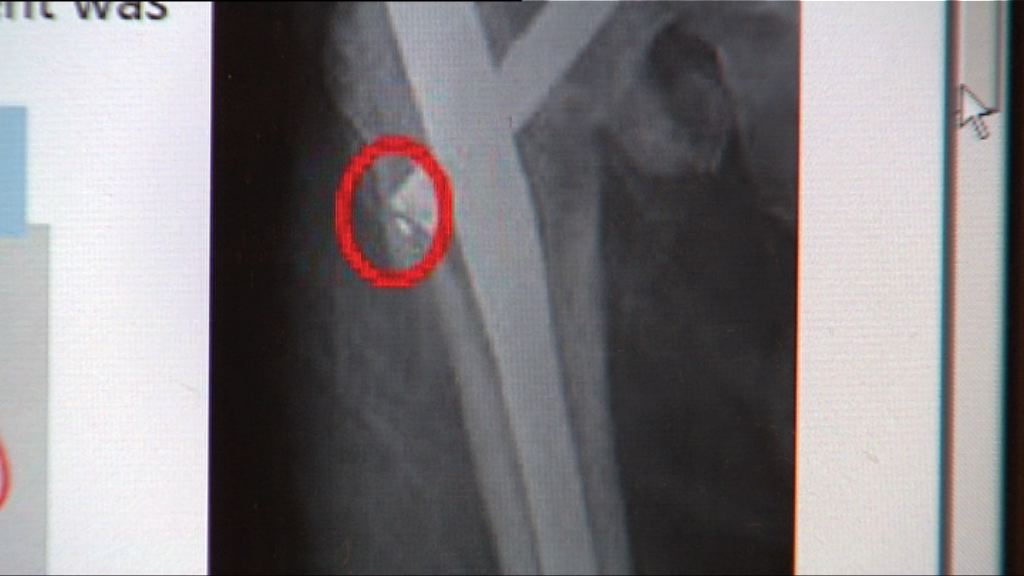

【Now新聞台】早前三間公立醫院先後未察覺病人肺部X光片出現異常陰影,延誤治療,醫管局委任委員會跟進。

醫管局委任根源分析委員會,由屯門醫院及博愛醫院放射科及核子醫學部部門主管王耀忠出任主席,率領四名不同專科委員會代表跟進事件。委員會將於八星期內完成報告及提出改善建議,而今次涉事的三間公立醫院分別為威爾斯親王醫院、瑪嘉烈醫院及瑪麗醫院。